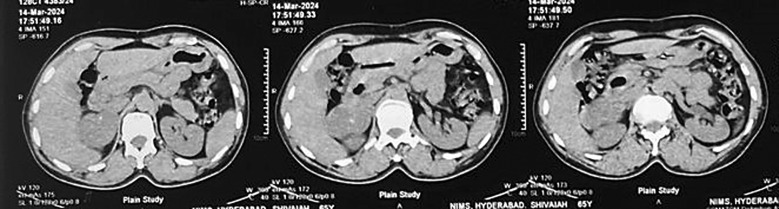

Case presentation: A male patient in his early 60s with a history of hypertension presented with an adrenal incidentaloma. Imaging revealed a well-defined, hypodense right adrenal mass (35 HU) with calcifications and an enlarged aortocaval lymph node, raising suspicion for carcinoma. Biochemical analysis showed a non-functional adrenal tumour. Intraoperatively, the mass appeared benign, but the lymph node deposit suggested malignancy. Histopathological examination confirmed right adrenal ganglioneuroma with metastatic deposits in the aortocaval lymph nodes. The patient recovered well postoperatively, with normal serum cortisol levels and no signs of recurrence at 6-month follow-up.